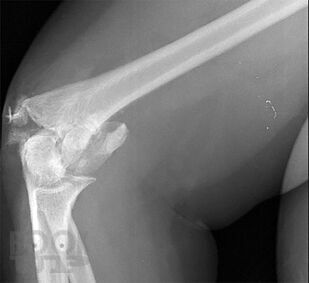

Учебно-практическое издание содержит ситуационные задания по наиболее распространенным и сложным разделам патологии опорно-двигательной системы (повреждения и заболевания верхних и нижних конечностей, позвоночника, повреждения и заболевания детского возраста и остеоонкология). Материал ситуационных заданий основывается на практическом опыте мирового сообщества травматологов-ортопедов. Для удобства восприятия материала эталоны ответов на ситуационные задания расположены в конце каждого задания. Практикум предназначен для ординаторов, аспирантов и врачей травматологов-ортопедов, обучающихся по специальности «Травматология и ортопедия».